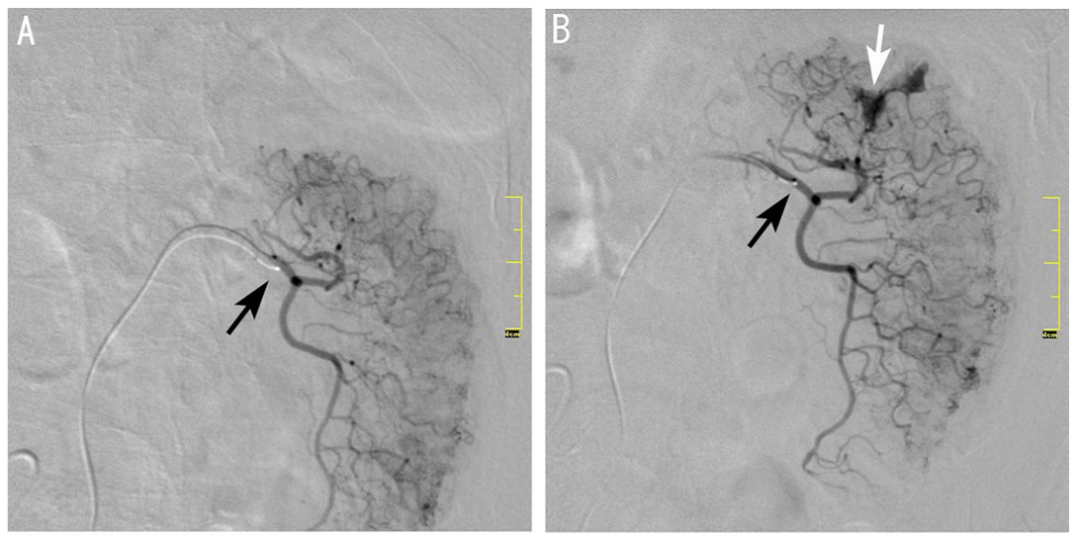

图:A:空肠动脉畸形;B回盲部肿瘤染色:CD:胃十二指肠动脉瘤

图:十二指肠溃疡出血,腹腔干造影,未见外渗,超选胃十二指肠动脉造影见外溢